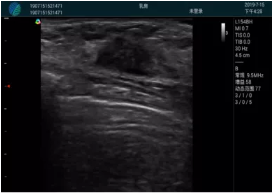

腺體內(nèi)部清晰顯示一低回聲塊影,形態(tài)不規(guī)則,邊界模糊,邊緣呈毛刺狀,內(nèi)部見砂礫樣鈣化

M20引導(dǎo)下穿刺活檢術(shù)

M20引導(dǎo)下平面內(nèi)穿刺取出的腫塊組織

M20查看:囊內(nèi)回聲均勻,邊界清晰,囊壁光滑

M20引導(dǎo)抽吸術(shù)后囊腫消失,原區(qū)域空腔形成,脂肪層與腺體層架構(gòu)發(fā)生改變

超聲以操作簡單、定位準(zhǔn)確、實(shí)時顯像、費(fèi)用低廉等優(yōu)勢,而成為麥默通乳腺活檢治療乳腺腫塊最常見的引導(dǎo)手段,已逐步在各大醫(yī)院開展此類手術(shù)。

2、超聲的可視化操作,能準(zhǔn)確的顯示病灶的位置、最大徑,選擇合適的刀具,決定切口的位置和方向,避開血管、減少出血危險(xiǎn)并實(shí)時觀察乳腺病灶的切割情況,避免造成腫塊組織殘留